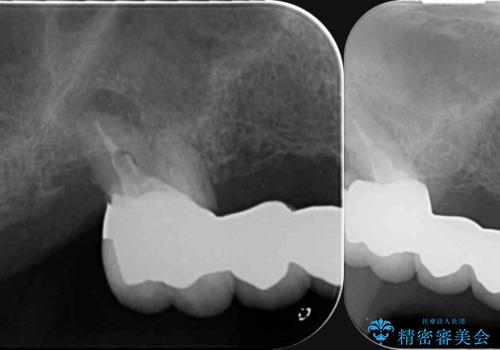

X線写真検査より、根尖病変に加え、歯周病による歯槽骨の吸収も見られ、歯質も薄く保存は難しいと判断し、

インプラント治療を進めることとなりました。